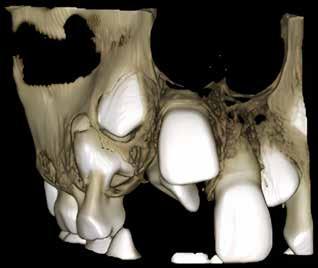

delta@delta-rengoering dk

deltaa@ddeltaa--rengoering d dk

www.delta-rengoering.dk

Hvis jobannoncen bliver indrykket på både Dentaljob.dk og i Tandlægebladet, får du 50 % rabat på annoncen i bladet

BAGGRUND – Centralt kæmpecellegranulom (Central giant cell granuloma – CGCG) er en sjælden, godartet læsion, som nærmest udelukkende er lokaliseret til kæberne. Det har kliniske, radiologiske eller histologiske ligheder med flere andre intraossøse læsioner. Ætiologien er stadig ukendt, men det viser sig, at genetiske mutationer er associeret med forekomsten af CGCG.

PATIENTTILFÆLDE – Tre drenge i alderen fem og seks år blev alle diagnosticeret med og behandlet for større CGCG-læsioner med få måneders mellemrum på Tand-, Mund- og Kæbekirurgisk Klinik, Aarhus Universitetshospital.

KONKLUSION – Det er yderst relevant at følge børn med spontant og tidligt tandtab i kommunal tandpleje. Ved mistanke om patologiske forandringer henvises til hurtig udredning og diagnostik i hospitalsregi for at klarlægge diagnose og minimere skader på blivende tandanlæg og omkringliggende strukturer.

EMNEORD Central giant cell granuloma | giant cell lesions | jaw neoplasm | benign bone diseases

CHRISTIAN LIND AXELGAARD, specialtandlæge i tand-, mund- og kæbekirurgi, Speciialklinik for kæbekirurgi, Silkeborg

KIMIE BOLS ØSTERGAARD, tandlæge i videreuddannelse til specialtandlæge i tand-, mund- og kæbekirurgi. Kæbekirurgisk Afdeling, Aalborg Universitetshospital

SVEN ERIK NØRHOLT, klinisk professor, specialtandlæge i tand-, mund- og kæbekirurgi, ph.d., overtandlæge, Afdeling for Tand-, Mund- og Kæbekirurgi, Aarhus Universitetshospital, og Sektion for Kæbekirurgi og Oral Medicin, Institut for Odontologi og Oral Sundhed, Aarhus Universitet

PER JOHAN SIXTEN BLOMLÖF, overtandlæge, docent, ph.d., specialtandlæge i tand-, mund- og kæbekirurgi, Afdeling for Tand-, Mund- og Kæbekirurgi, Aarhus Universitetshospital

STEEN BÆRENTZEN, overlæge, Patologiafdelingen, Aarhus Universitetshospital

OTTO THORSSON, specialtandlæge i tand-, mund- og kæbekirurgi, Afdeling for Tand-, Mund- og Kæbekirurgi, Aarhus Universitetshospital Accepteret til publikation den 13. maj 2025 Tandlægebladet 2025;129:928-34

CKorrespondanceansvarlig førsteforfatter: CHRISTIAN LIND AXELGAARD christianlindaxelgaard@gmail.com

ENTRALT KÆMPECELLEGRANULOM (CGCG) er en sjældent forekommende, benign, destruktiv læsion i kæberne, som af WHO karakteriseres ved en uindkapslet spredning af mononukleære spindelformede og polygonale celler med tilstedeværelsen af osteoklastlignende, multinukleære kæmpeceller i en vaskulær baggrund (1). CGCG udgør ca. 7 % af alle benigne, tumorøse læsioner i kæberne (2). CGCG ses med øget hyppighed ved patienter med RASopatier, som er fænotypisk homogene grupper af genetiske syndromer, forårsaget af patogenetiske stamcellevariationer i dele af RAS/mitogen-activated protein kinase (RAS/MAPK) pathway (Faktaboks) (3); heriblandt neurofibromatose type 1 (NF1) og Noonans syndrom (NS) (4). CGCG forekommer også sporadisk uden kendte stamcellemutationer. Ved patienter med sporadiske CGCG ses også ofte genmutationer i MAPK-pathway proteiner som KRAS, FGFR1 eller TRPV4, hvilket tyder på en genetisk årsag for udvikling af CGCG (5-8).

MAPK-pathway’en er en af de vigtigste og mest undersøgte signaleringspathways. Den er centrum i et molekylært signaleringsnetværk, der styrer vækst, proliferation, differentiering og apoptose. Meget forenklet signalerer den gennem tyrosinkinasereceptorer, der fosforylerer et målprotein som respons på en stimulus, og dette sætter gang i reaktioner, som afgrænses ved defosforylering af et protein downstream. Den fungerer således som en kontakt, der kan tænde og slukke. Hvis der er mutationer i et af proteinerne i denne pathway, kan denne sidde fast i tændt eller slukket tilstand (9).

Sporadiske tilfælde af CGCG forekommer oftest i den anteriore del af mandiblen og debuterer typisk i de første tre årtier af livet (5). I de syndromiske tilfælde ses mere end 90 % posteriort for hjørnetænderne (10).

Læsionerne vokser normalt langsomt, men aggressiv adfærd er ikke ualmindeligt (2). CGCG opdeles i nonaggressive og aggressive subtyper (11), hvilket er vigtigt for valget af behandling, da de aggressive subtyper har en højere recidivtendens (10,12). Histologisk er CGCG identisk med ”Brown tumor”, som ses ved hyperparatyroidisme, men denne tilstand rammer typisk patienter over 50 år. Derfor er det vigtigt med en

Fig. 1. Centralt kæmpecellegranulom i kæbe (A) med ossøs kæmpecelletumor/ osteoklastom i os sacrum til sammenligning (B). Kæmpeceller af osteoklastlignende type (tykke pile) ses af lille til moderat størrelse i kæmpecellegranulomet og af moderat til stor størrelse i kæmpecelletumorer. De mononukleære celler (tynde pile) ses tenformede i fibrøs matrix i kæmpecellegranulomet og anderledes plumpe uden matrixdannelse i kæmpecelletumoren.

Fig. 1. Central giant cell granuloma in the jaw (A) with giant cell tumor of bone/ osteoclastoma in the sacrum for comparison (B). Giant cells of osteoclast-like type (thick arrows) are seen in small to moderate size in the giant cell granuloma and in moderate to large size in the giant cell tumor. The mononuclear cells (thin arrows) appear spindle-shaped in a fibrous matrix in the giant cell granuloma and rather plump without matrix formation in the giant cell tumor.

endokrinologisk udredning for at sikre korrekt diagnose (13). Yderligere er det væsentligt at pointere, at CGCG ikke er det samme som den ossøse kæmpecelletumor/osteoklastom (Fig 1.), der praktisk taget aldrig ses i kæberne, men i stedet i lange rørknoglers epifyser og aksiale skelet og har en helt anden genetisk baggrund med mutation i H3F3A-genet, er endnu mere lokalt aggressiv og endda har en ganske lille risiko for hæmatogen metastasering og malign omdannelse (14).

PATIENTTILFÆLDE 1

Anamnese

En seksårig dreng blev henvist til en second opinion fra Pædiatrisk Afdeling, Aalborg Universitetshospital, hvortil patienten i første omgang var henvist med mistanke om malignitet eller kæmpecelletumor. Patienten havde spontant tandtab i fireårsalderen uden andre symptomer.

Klinik

Ved klinisk undersøgelse blev der observeret en blålig hævelse anteriort i underkæbefrontregionen.

Røntgen

CT-scanning viste diffus osteolyse i mandiblen fra midtlinjen og mod venstre, med involvering af -1,2. Destruktionen og ekspansionen havde ikke forårsaget resorption af tænderne (Fig. 2-3).

Histologi

Tidligere biopsi havde vist CGCG eller perifert kæmpecellegranulom. Ved ny patologisk gennemgang af præparatet blev CGCG bekræftet. Molekylærpatologisk analyse viste en KRASmutation, der understøttede diagnosen.

Patienttilfælde 1 – Præoperativ CT-scanning

Forløb